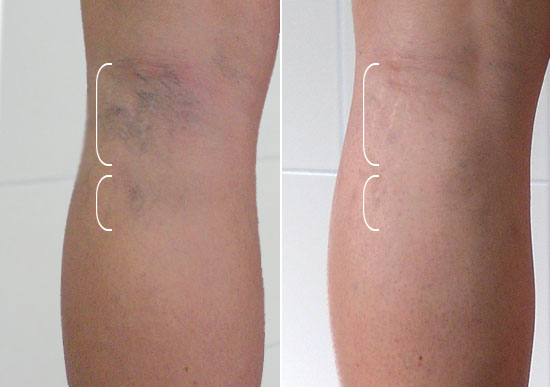

- Для лечения варикозного расширения вен.

- Для устранения симптомов венозной недостаточности.

При систематическом использовании наблюдается уменьшение болевых ощущений, отеков и чувства тяжести в конечностях, а также положительное влияние на физическое и эмоциональное состояние. Возможен прием во время беременности.

Повышает устойчивость капилляров, снимает воспалительные процессы, восстанавливает кровообращение. Часто используется в составе комплексного лечения геморроидальных узлов и венозной недостаточности.

Способствует восстановлению стенок сосудов, снимает воспалительные процессы, нормализует состав крови и улучшает качество эритроцитов. Используется при геморрое, варикозном расширении вен и трофических язвах.